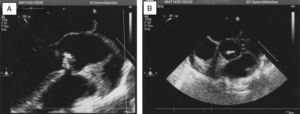

We present the case of a 36-year-old woman who presented with arthritis of her left ankle. Her history included a pregnancy that had ended in delivery 5 months earlier. Since then, she had had a recurrent fever syndrome, with polyarthralgia and distal swelling of her fingers and left ankle. Physical examination revealed arthritis in left ankle, acropachy affecting the fingers of both hands, a diastolic murmur in the aortic area and crackling rales in both lung bases. Laboratory tests showed anemia of chronic disease (hemoglobin: 9.8g/dL), elevated acute phase reactants (erythrocyte sedimentation rate: 120mm/h and C-reactive protein: 107.34mg/L), and negative autoantibody tests (rheumatoid factor, antinuclear antibodies and anti-cyclic citrullinated peptide antibodies). Musculoskeletal ultrasound confirmed the arthritis in left ankle (power Doppler signal). An echocardiogram revealed the presence of vegetation on the partially calcified, bicuspid aortic valve, partial prolapse of this valve, and severe aortic regurgitation, with no evidence of heart failure (Fig. 1). The blood cultures performed resulted in the isolation of L. monocytogenes.